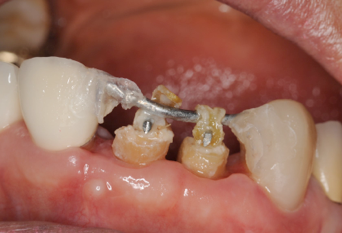

右の前歯二本がボッキリおれてしまいました。幸い歯の根っ子は折れていませんでしたから、抜歯せずに残せそうですが.........

歯が折れて根っ子が少しだけ歯茎からでている状態。

虫歯でもそうですが、こうなるとこのまま差し歯をいれてもすぐ外れるといったトラブルが起こります